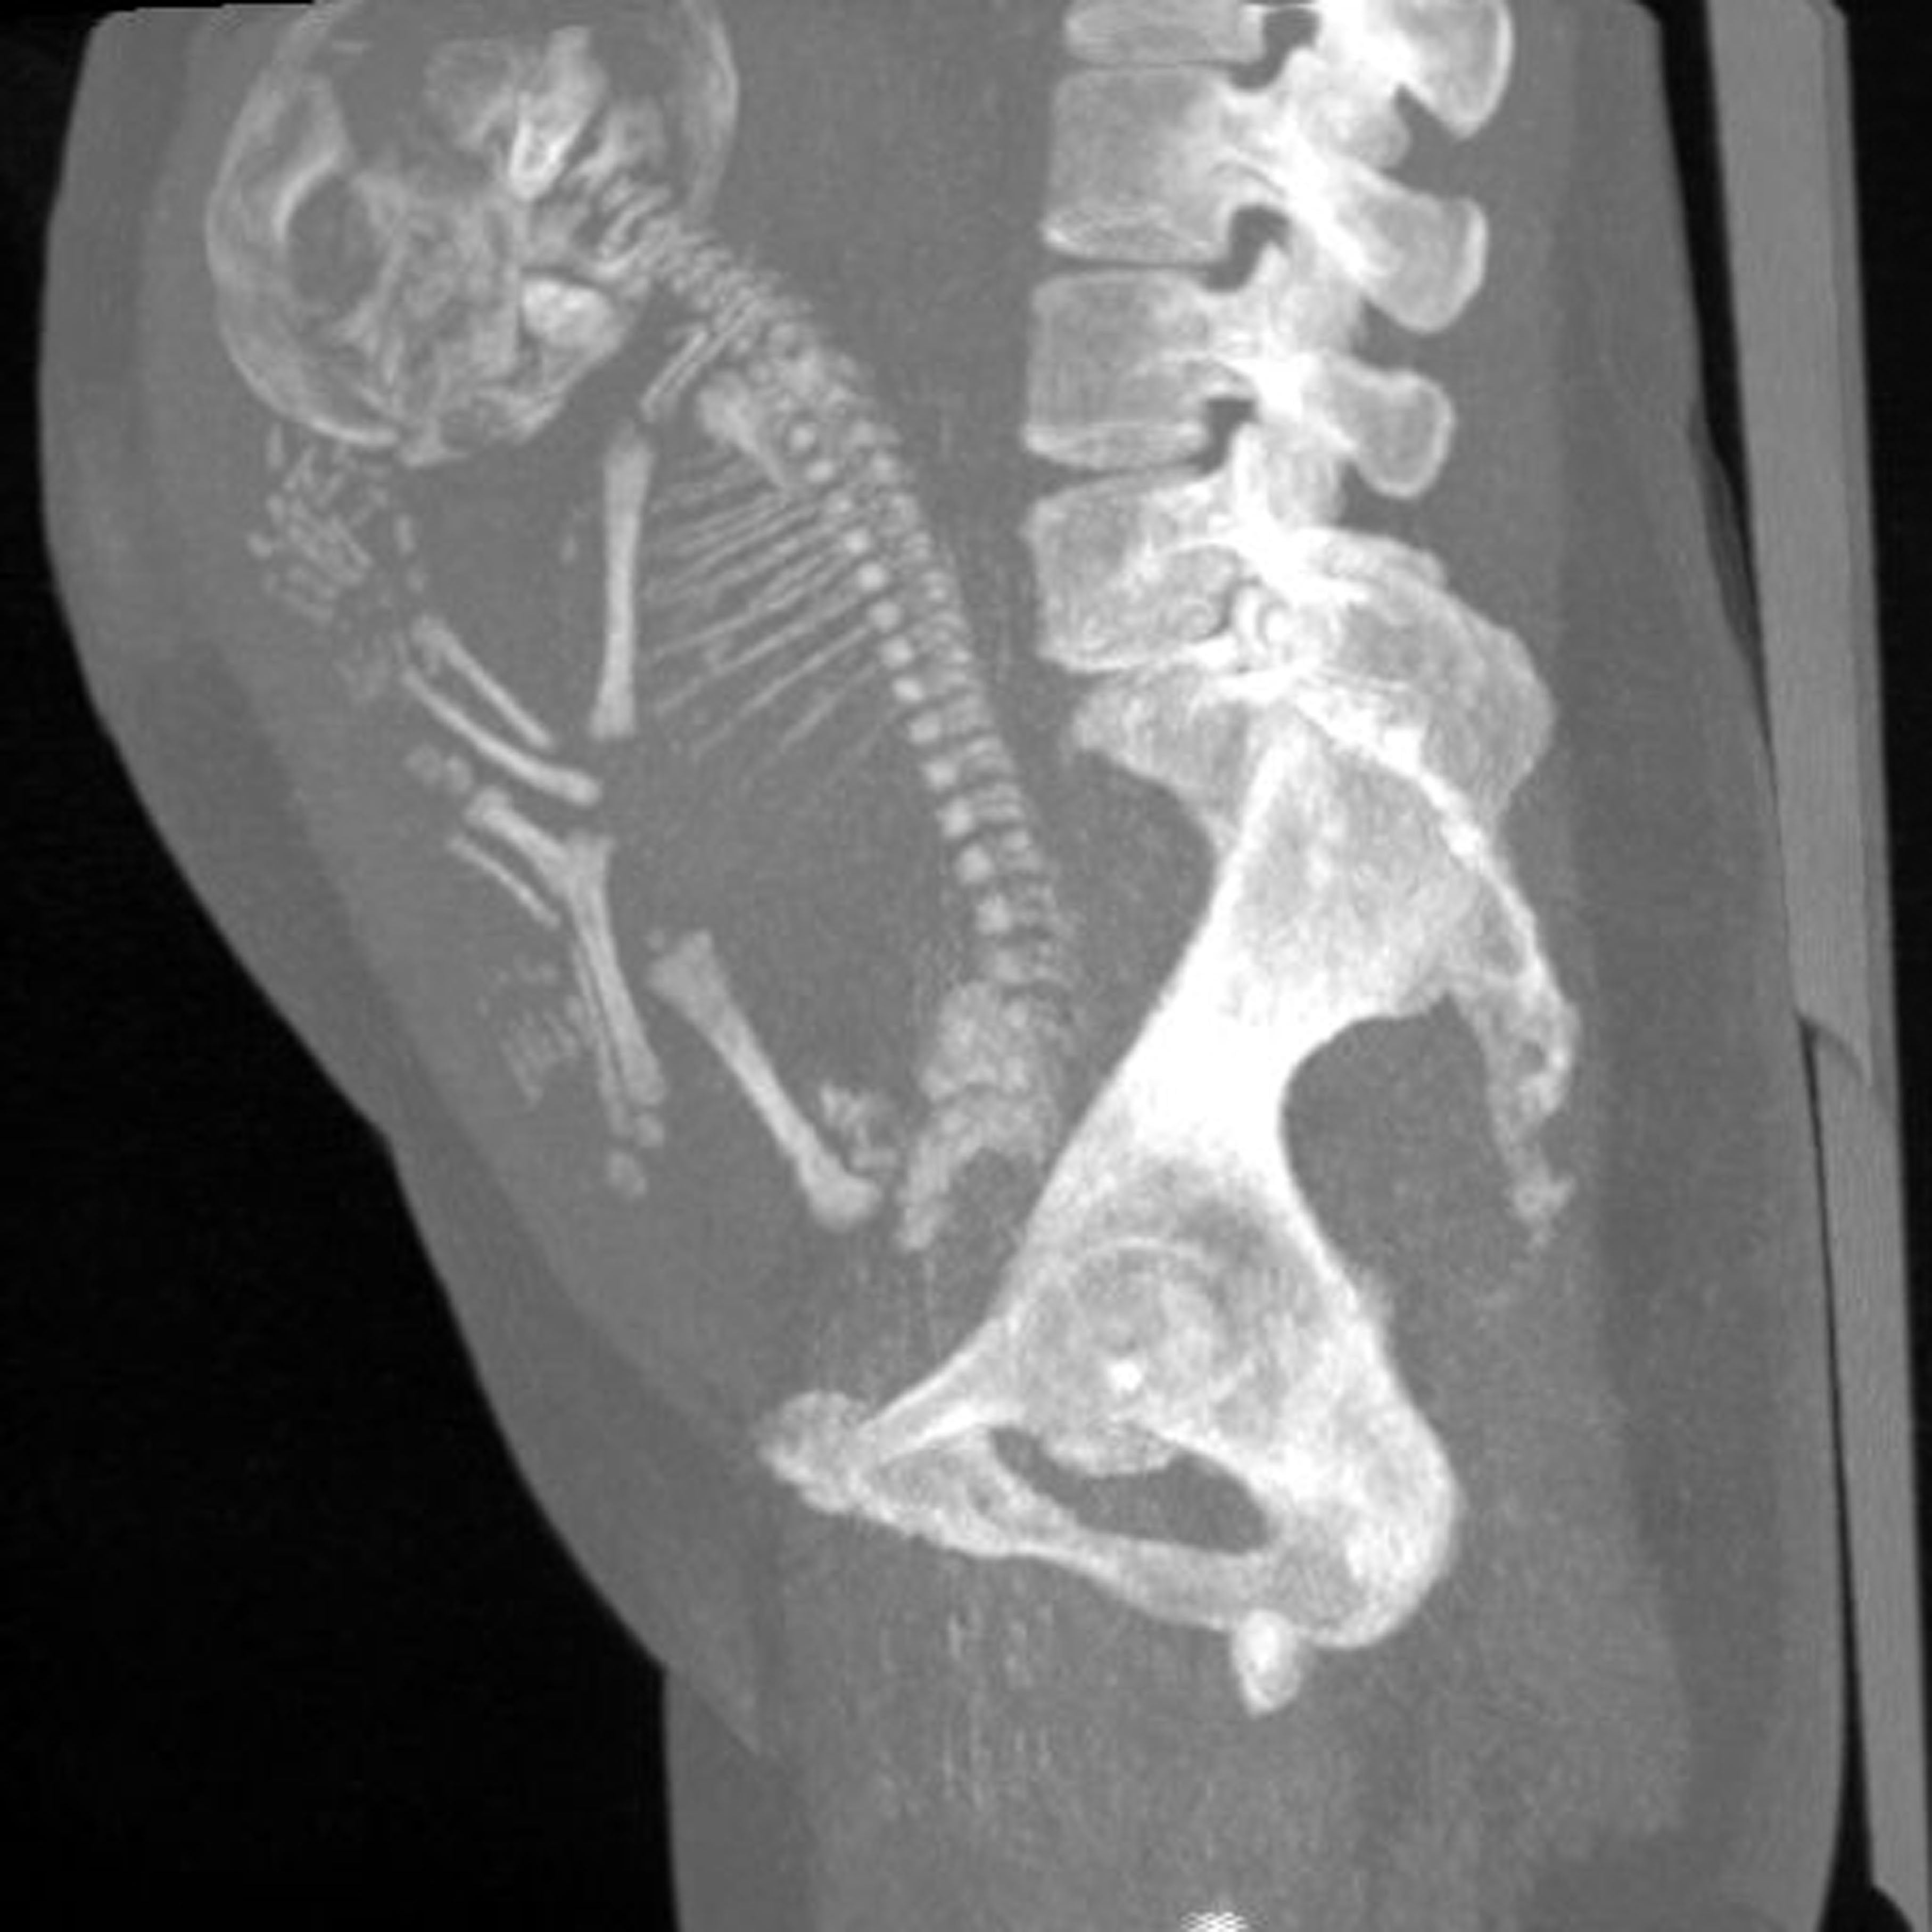

En cuanto a la explicación científica de este inusual hecho, los médicos creen que el feto se calcificó, en un raro evento llamado lithopaedion, que es extraordinariamente raro, en el que el exterior del cuerpo del feto se calcifica como parte del intento del cuerpo de la madre de protegerse.

Es así como parte de una reacción a un cuerpo extraño para proteger a la madre del tejido muerto y de contraer una infección. Los médicos calculan que el bebé murió y fue momificado en la semana 40 del embarazo después de no desarrollarse normalmente, según el Daily Star.

Según Public Med Central, este inusual caso médico se puede describir como un embarazo ectópico abdominal en el que el feto muere, pero no puede ser reabsorbido por el cuerpo de la madre. El feto muerto queda retenido en la cavidad abdominal, formando una capa de calcio a su alrededor.

El litopedion se ha descrito en mujeres con edades comprendidas entre 23 y 100 años, siendo dos tercios de ellas mayores de 40 años. El período de retención del feto fue de 4 a 60 años. En este caso, se desconoce el período de retención exacto, pero es razonable pensar que podría ser al menos 40 años.

La tomografía computarizada y la resonancia magnética son capaces de llegar a un diagnóstico concluyente y permiten una mayor caracterización de la masa, ayudan al diagnóstico de adherencia, definen la afectación de estructuras adyacentes y estiman la edad gestacional fetal midiendo la longitud femoral.